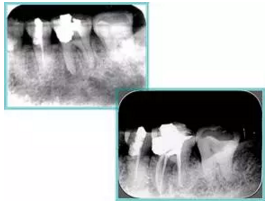

上圖為干髓治療后牙齒,齲齒疏通后進(jìn)行根管充填。

如圖為塑化加根充處理后牙齒 X 線片。